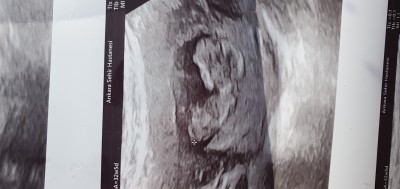

image

kız bence :D

Ama  ginede kiz diyorum  karin  bolgesi  duz  inis  yok  kizlarda  boyle  oluyor